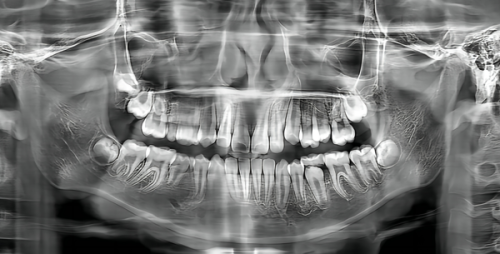

牙齿问题是特别多人都面临的难题。牙齿疼痛可能会让人坐立难安,重度影响生活质量;牙齿不整齐不仅影响美观,还可能导致清洁困难,增加龋齿和牙周炎的风险;牙齿缺失则会影响咀嚼功能,进而影响消化。面对这些问题,人们往往会感到焦虑,担心找不到专精的医生和合适的治疗方案,害怕治疗过程中出现意外,尤其是一些复杂的牙齿问题,让人更加不知所措。

天津市河西区华奥茂和口腔门诊部拥有一支专精的团队。门诊部的医生都具备丰富的临床经验和专精知识,他们经过严格的专精培训,能够正确诊断各种牙齿问题,并制定个性化的治疗方案。无论是简单的洗牙、补牙,还是复杂的正畸、种植牙手术,医生们都能熟练操作。而且,医生们注重与患者的沟通,会详细了解患者的需求和担忧,让患者在治疗前就对治疗过程和成效有清晰的认识,从而减轻患者的焦虑。